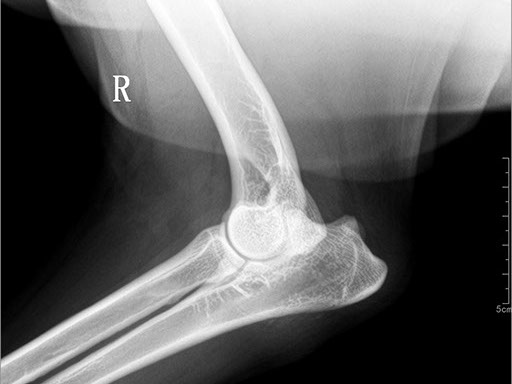

Коллиматорный прицел формирует пучок рентгеновского излучения на участок исследования. Проходя через ткани тела, излучение попадает на плоскопанельный цифровой детектор, который, в свою очередь, передает сигналы на компьютер.

В считанные секунды полученные данные обрабатываются компьютером посредством установленной на него программы визуализации, и сформированное клиническое изображение выводится на монитор лаборанта.

Клинические изображения (снимки) можно напечатать на принтере, сохранить в архиве или отправить по сети коллегам для оперативного консилиума.